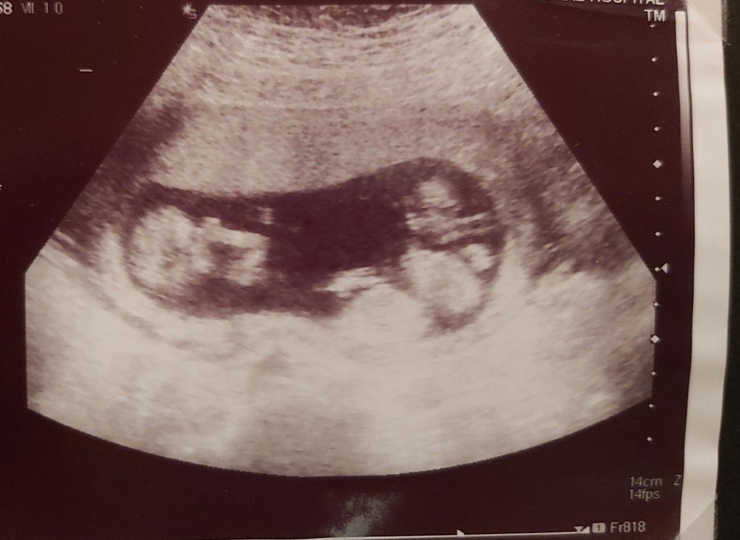

From the beginning, Jo was being scanned to check our babies’ development up to three times a week. At one of these appointments, we found out we were having two identical boys (in one sac) and a singleton boy (in his own little sac).  At first the checks were reassuring and it was lovely to see the babies develop, but it began to heighten every emotion and fear we already had.